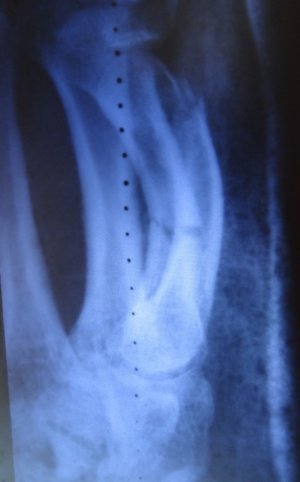

Обратился к травматологу по месту жительства и на 6 день после получения травмы сделали контр.снимок:

Доктор взглянув на НЕЗНАЧИТЕЛЬНОЕ СМЕЩЕНИЕ сказал что нужна репозиция, сделал закрытую репозицию отломков и наложил лонгету на 4 и 5 пальцы в вытянутом состоянии, вот снимки сразу после наложения лонгеты: